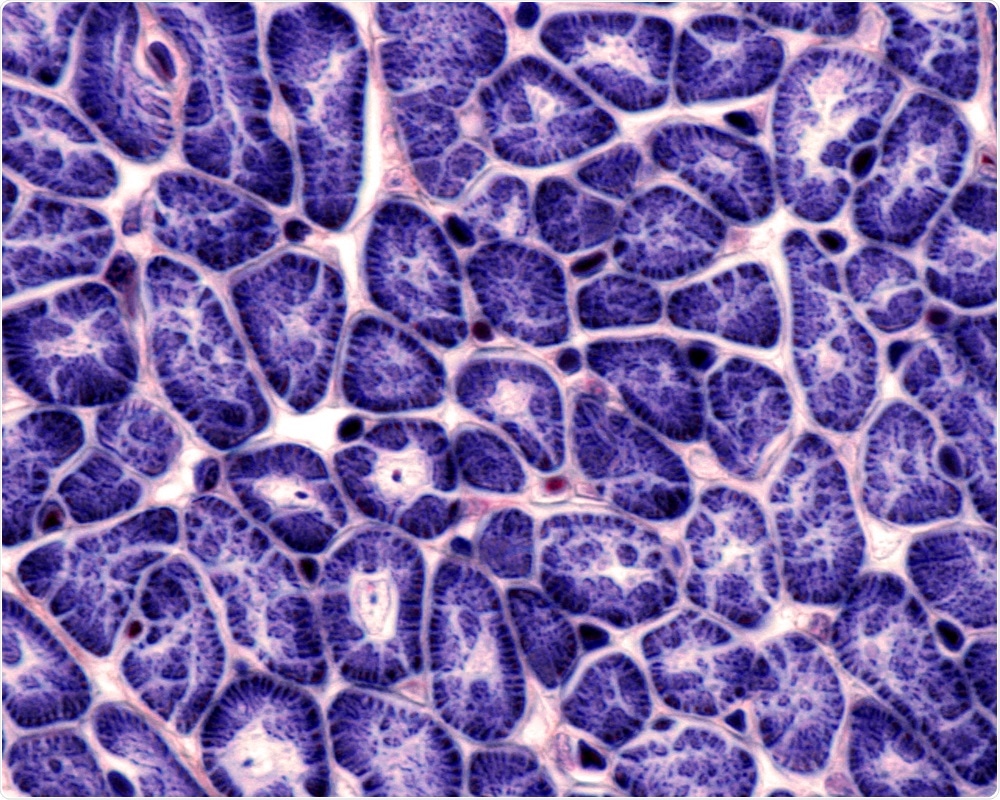

Jose Luis Calvo | Shutterstock

The heart muscle cells or cardiomyocytes, which were derived from human induced pluripotent stem cells (hiPSCs), were grown to form 3D heart tissue that beats and has contractile force, gene expression, and drug responses that are similar to those seen in real human atria.